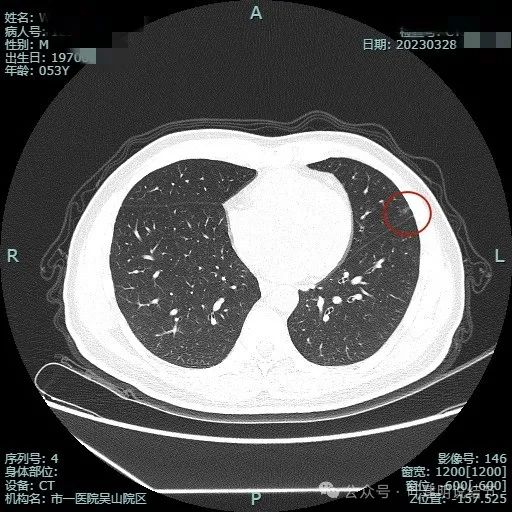

2023年3月影像展示:

病灶出现,密度淡,靠叶间裂较近,整体轮廓较为清楚。

密度纯,但不是太均匀,感觉稍不均,瘤肺边界清,贴胸膜近。

与叶间裂也是贴着的。